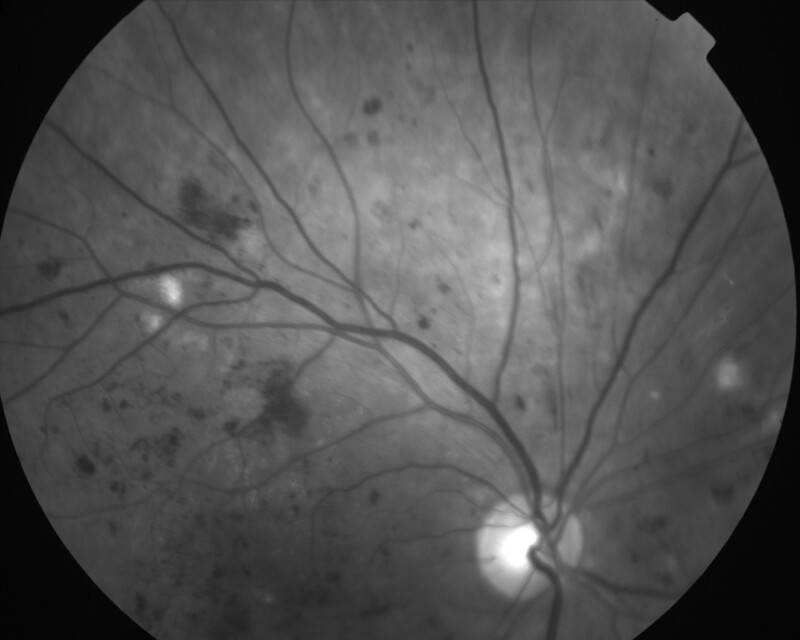

RETINOPATHIE DIABETIQUE NON PROLIFERANTE SEVERE

IMG0003.JPG